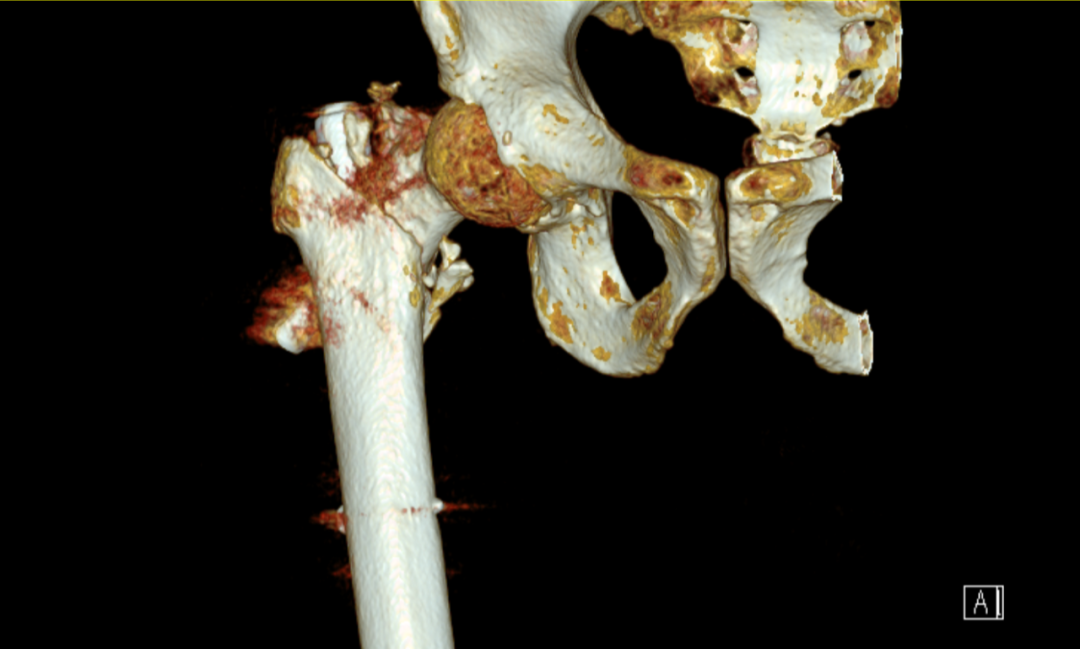

入院后,科主任魏國華帶領(lǐng)關(guān)節(jié)骨科醫(yī)護(hù)團(tuán)隊積極完善相關(guān)檢查,充分發(fā)揮中醫(yī)骨傷的治療優(yōu)勢,做好充分術(shù)前準(zhǔn)備,根據(jù)患者病情科學(xué)制定個性化治療方案,排除手術(shù)禁忌癥后行右側(cè)PFNA內(nèi)固定取出+右側(cè)人工全髖關(guān)節(jié)置換術(shù),術(shù)程順利,在醫(yī)護(hù)人員的精心治療和護(hù)理下,患者術(shù)后第二天即可扶助行器下地行走,現(xiàn)恢復(fù)良好,已出院。

術(shù)后: